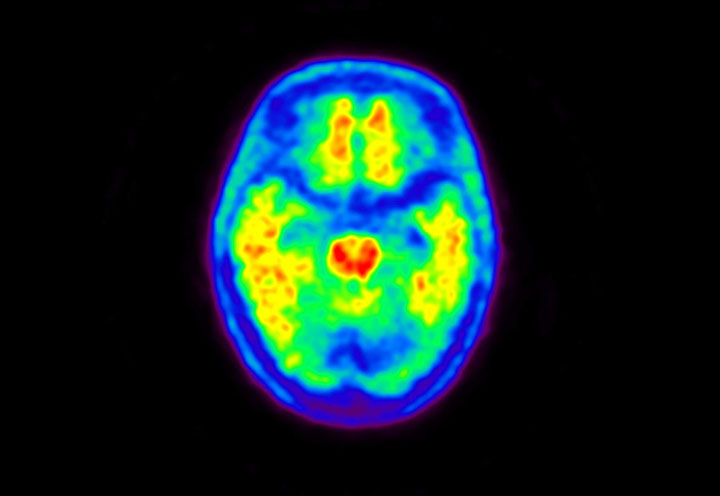

Head / Case5 : Amyloid

Axial

Courtesy : Kindai University Hospital

- Imaging protocol

- Injected dose: 4.27 MBq/kg, 18F-Flutemetamol

- Uptake time: 99 minutes

- Scan time: 20 minutes